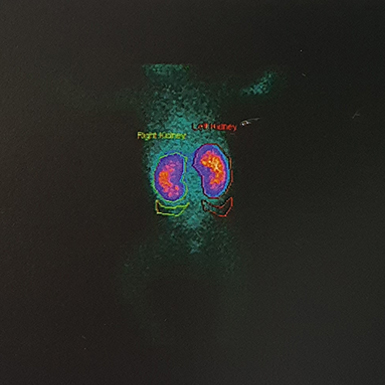

هل يجب إجراء تصوير (Échographie) من أجل التشخيص؟

ليس من الضروري إجراء تصوير طبي لتشخيص التهاب الحويضة والكلية الحاد (Pyélonéphrite aiguë)، إلا أن التصوير قد يكون مفيدًا في بعض الحالات الصعبة أو الغامضة.

تعدّ الموجات فوق الصوتية للكلية (Échographie rénale) مفيدة بشكل خاص لاكتشاف أي تشوّه خلقي في المسالك البولية، إذ إن وجود مثل هذه التشوهات يزيد من خطر الإصابة بعدوى المسالك البولية.

ويُفضَّل أن تبدأ فحوصات الكشف عن التشوهات الكلوية بالموجات فوق الصوتية، بعد فترة من انتهاء نوبة العدوى، لضمان دقة النتائج وتجنّب تأثير الالتهاب الحالي على الصورة التشخيصية.